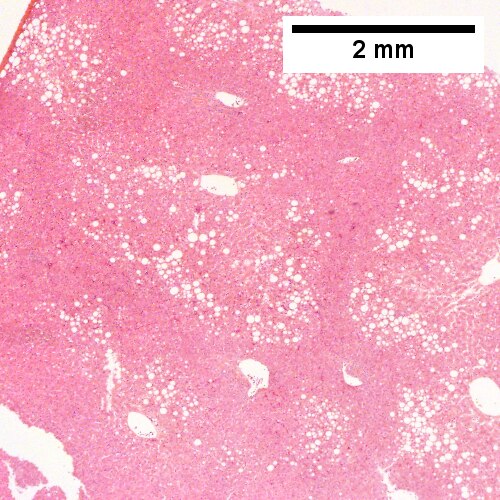

A. Panacinar steatosis with unremarkable, small triads (40X).

Steatohepatitis Brunt necroinflammatory grade 3, Brunt fibrosis stage 1. A. Panacinar steatosis with unremarkable, small triads. B. Ballooning degeneration, with cytoplasmic tufts [arrows]. C. Lipogranuloma. D. Triad with mild chronic inflammation without interface hepatitis.

A. Steatosis afflicts almost all hepatocytes (pan-acinar) (Row 1 Left 40X).

Steatohepatitis. Brunt necroinflammatory grade 3, Brunt fibrosis stage 3. A. Steatosis afflicts almost all hepatocytes (pan-acinar). B. An isolated septal duct with concentric fibrosis [arrow] should not result in a diagnosis of primary sclerosing cholangitis. The woman who underwent the biopsy had a normal bilirubin level, a normal alkaline phosphatase level, and only slightly elevated transaminase levels. C. Cytoplasmic tufts [arrows] prove ballooning degeneration. D. PAS with diastase shows PAS-D Kupffer cells (arrows). E. Reticulin shows thick black lines [red arrows] of collapse, without portal central bridging. The apparent loss of reticulin due to steatosis [double head cyan arrow] should not be considered regeneration or hepatoma. F. Trichrome shows a bridge [arrow].